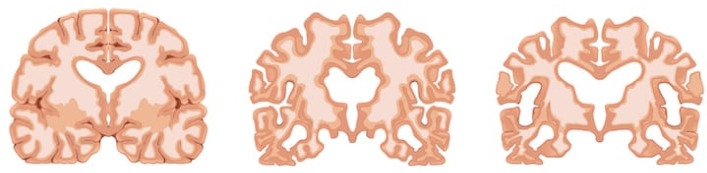

제일 왼쪽 정상인의 뇌, 가운데 중간 정도 치매 환자의 뇌, 제일 오른쪽은 중증 치매 환자의 뇌

담당 의사 선생님이 알츠하이머 치매의 진행 과정을 설명하셨다. 위의 사진 제일 왼쪽 정상인의 뇌는 밀도가 촘촘하고 빈 곳이 없다. 중간 정도 치매가 진행된 사람의 뇌는 듬성듬성 구멍이 커졌다. 마지막 제일 오른쪽의 중증 치매 환자의 뇌는 크기도 확연히 작아졌고, 신경세포가 사라진 빈 곳이 너무 많다. 이 정도 되면 인지 능력과 기억력이 상당히 떨어진 상태라 혼자서 생활하는 것이 불가능하다.